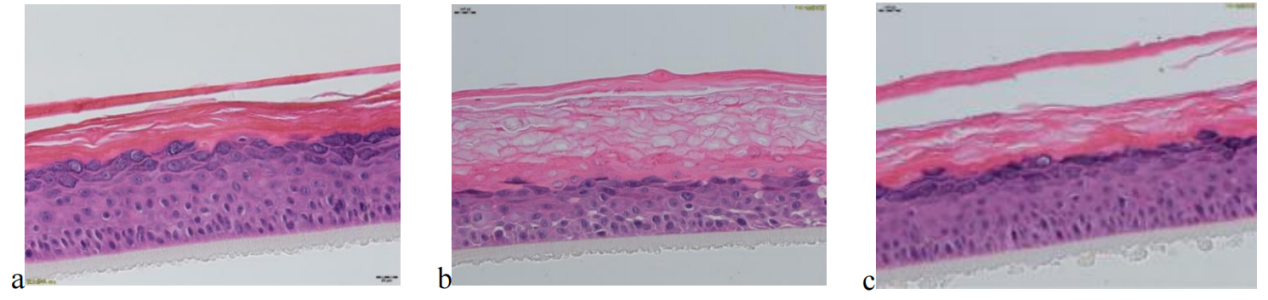

待测活性物与BAP联合作用于EpiKutis® 皮肤模型后,形态学结果见图6。与空白对照组(Control)相比,刺激组(BAP)的角质层增厚、排列疏松、空泡明显且分化不完全;活细胞层(颗粒层、棘层、基底层)活细胞数目减少,基底层细胞空泡明显,排列疏散。

图 6 不同处理条件下表皮模型的形态学变化情况(放大40倍)

(a.空白对照组,b.BAP刺激组,c.待测活性物组)